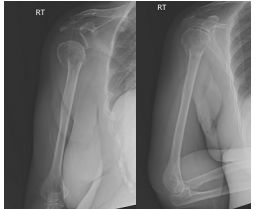

53 58歲女性昨日跌倒後右肩疼痛活動角度受限,今日因右上臂瘀青腫脹就診,X光如附圖所示,下列敘 述何者正確? (A)X光顯示右側肱骨解剖頸外展型骨折 (B)該骨折又稱作臑骨肩端骨折 (C)該患者右肩外觀會明顯呈現方肩畸形 (D)該類型骨折如果輕度成角與側方移位發生在老年人需積極復位